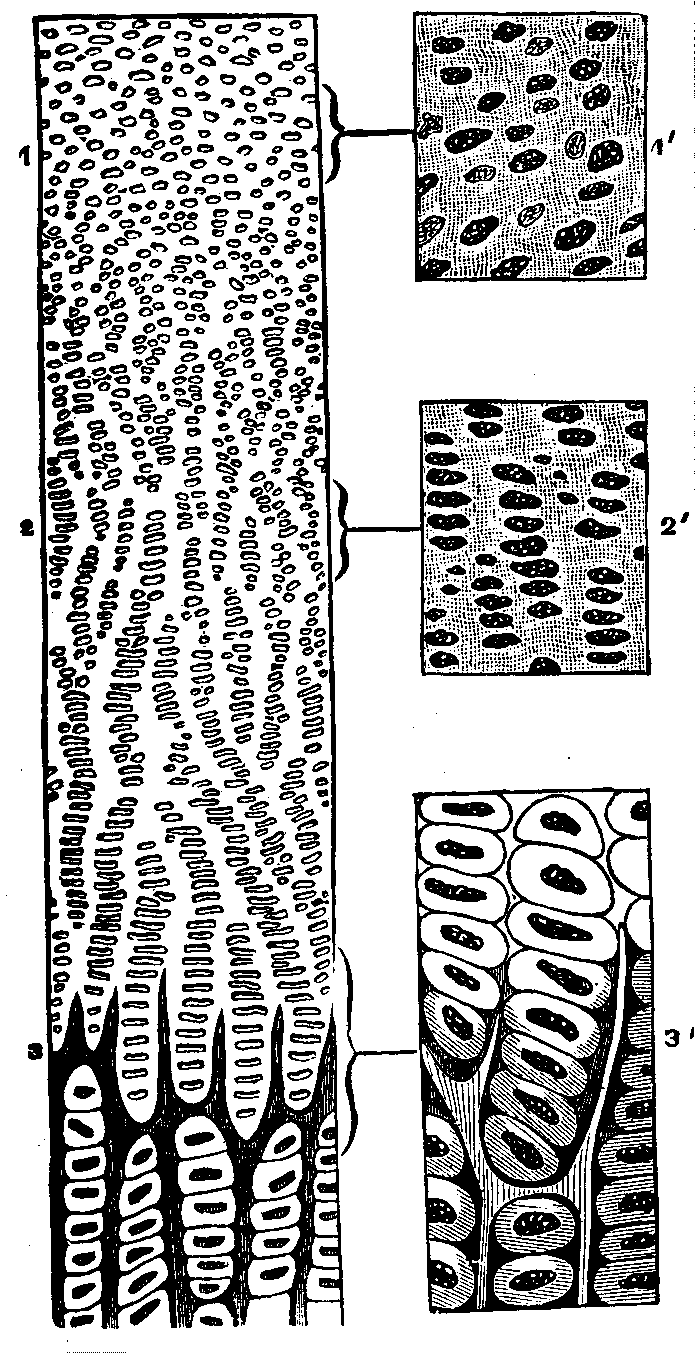

Fig. 7. Vertical section of

cartilage near the surface of ossification. 1. Ordinary appearance

of the temporary cartilage. 1'. Portion of the same more highly

magnified. 2. The cells beginning to form into concentric zones.

2'. Portion more magnified. 3. The ossification is extending

in the inter-cellular spaces, and the rows of cells are seen resting in the

cavities so formed, the nuclei being more separated than above. 3'.

Portion of the same more highly magnified.